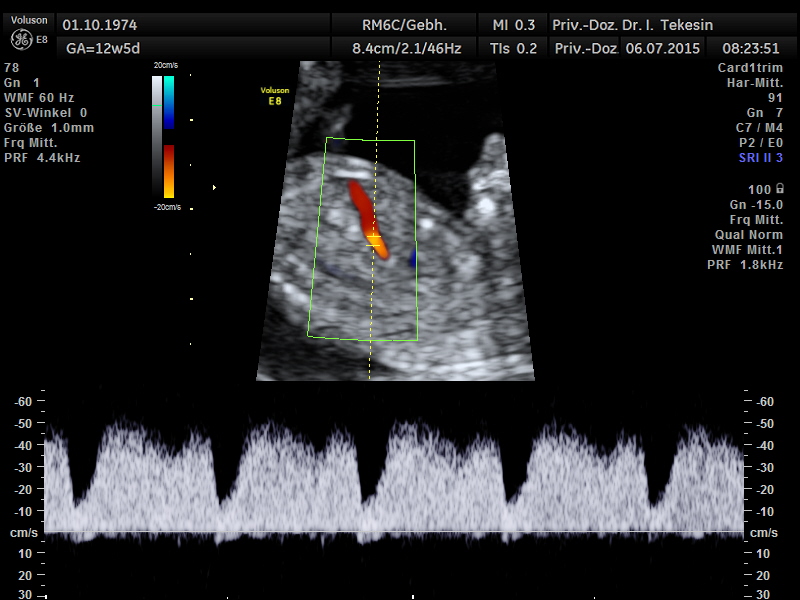

Normaler Blutfluss über die rechte Herzklappe (Trikuspitalklappe - TK) in der 13. Woche

Darstellung des TK in der 13. SSW mittels Farb-Doppler